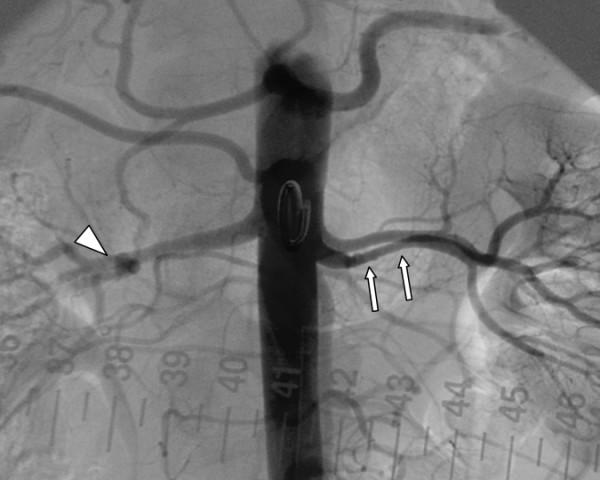

In this report, we present a relatively uncommon case of renovascular hypertension in a 35-year-old female with a history of intractable hypertension as a result of fibromuscular dysplasia involving an accessory renal artery. Selective renal angiography was performed and revealed a single renal artery on the right and two renal arteries supplying the left kidney, upper and lower poles. Selective renal angiography showed the typical fibromuscular dysplasia lesion characterized by its classic "string of beads" appearance, consisting of alternating areas of narrowing and dilatation, located in the middle portion of the lower left renal artery (accessory artery) associated with moderate stenosis. Percutaneous balloon dilatation of the stenotic lesion was successfully performed. Following angioplasty, her blood pressure normalized over a period of several months using a single antihypertensive medication (rather than 3 medications).

在本报告中,我们呈现了一例相对罕见的肾血管性高血压病例,患者为一名35岁女性,有顽固性高血压病史,病因是累及副肾动脉的纤维肌发育不良。进行了选择性肾血管造影,结果显示右侧有一条肾动脉,左侧肾脏的上极和下极由两条肾动脉供血。选择性肾血管造影显示典型的纤维肌发育不良病变,其特征为经典的“串珠样”表现,由狭窄和扩张交替区域组成,位于左肾下极(副肾动脉)中部,伴有中度狭窄。成功地对狭窄病变进行了经皮球囊扩张。血管成形术后,她仅使用一种抗高血压药物(而非三种药物),血压在几个月内恢复正常。